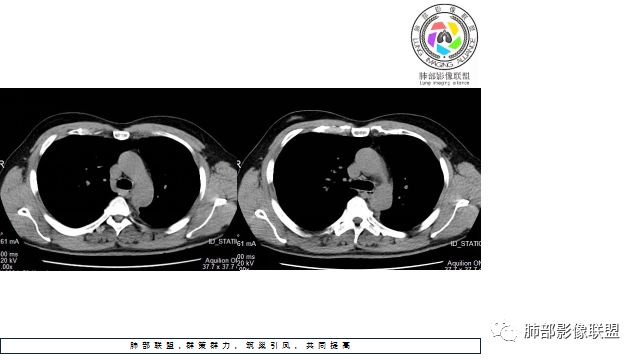

1.左下肺门区巨大肿块,支气管显示不清,轻度阻塞性炎症,没有明显肺不张,提示管腔受压狭窄可能性大于堵塞,这较少见于鳞癌。

2.病灶边缘光滑,未见明显分叶、毛刺,未见明显强化,这符合腺癌影像学特点,却符合神经内分泌癌表现。

3.病灶内密度均匀,轻到中度均匀强化,大病灶未见明显液化坏死区及空洞,不符合鳞癌而符合小细胞肺癌特点。

4.病灶内有肺动脉走形,血管局部受压,未见破坏,病灶乏血供,呈血管包埋或血管造影征;侵袭性力强及破坏力弱、血管漂浮都符合SCLC,所以鳞癌的可能性也不大。

5.左肺门块影或淋巴结肿大,竭力挤兑肺门血管结构,呈冰冻肺门;有时候SCLC可以单独呈现冰冻肺门,而没有没有冰冻纵隔。

7.须特别注意的是,肺门区的融合块影,不排除它可能仅仅为转移淋巴结。